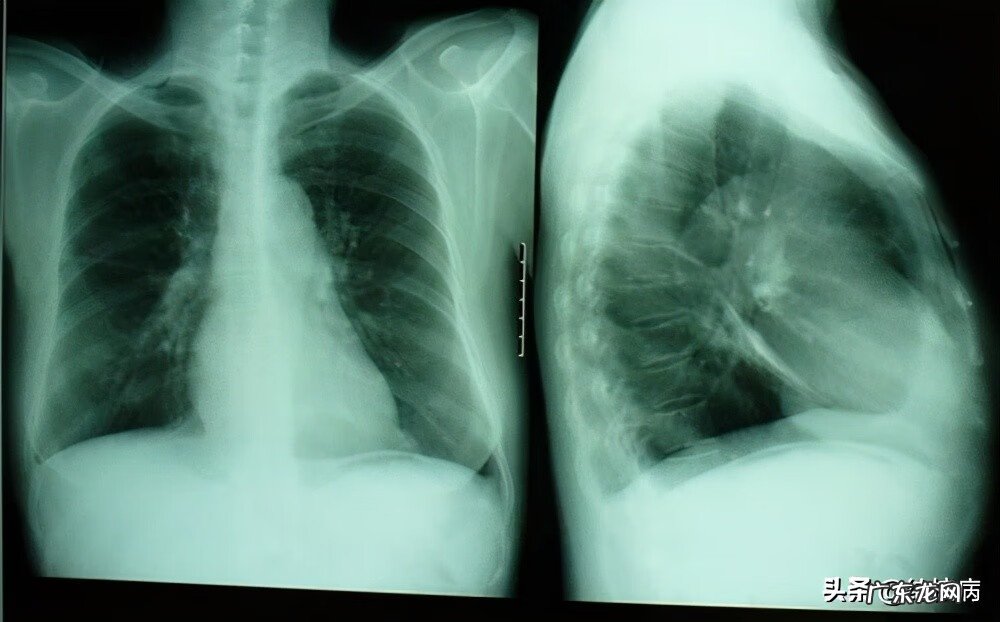

结核性胸膜炎的早期症状主要有:发烧、咳嗽、胸闷和胸痛 。一旦患病部位出现胸水,胸痛可以明显减轻,但因胸水量的不同,可以出现不同程度的胸闷症状,胸水越多,胸闷症状越明显 。

【胸膜炎的早期症状及表现 胸膜炎的症状与表现 早期症状】